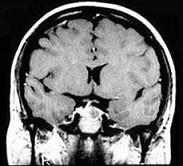

问题 患者因库欣病行垂体腺瘤切除术后1年,定期随访疾病是否复发,需要定期随访疗效的指标是()

选项 A.I吸收率 B.T、T水平 C.尿17羟、尿17酮水平 D.全天血糖监测 E.血浆皮质醇节律

答案 E